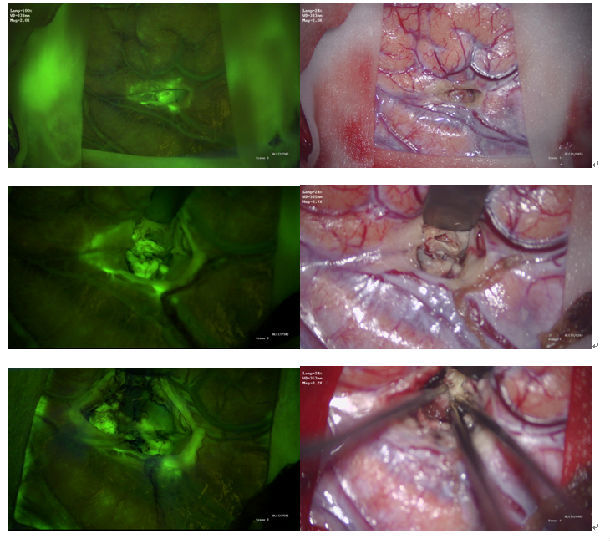

1.切开硬膜后,皮层表面未见到明显肿瘤组织,但在荧光下发现额下回后部皮层深部可见隐约的淡黄色荧光,提示肿瘤所在部位。

2.切开蛛网膜后,向深部分离,切开囊壁,可见淡黄色囊液流出。囊液本身在荧光下无显影。

3.吸除部分囊液后,可见肿瘤浅部和深部囊壁均呈绿色荧光染色。

4. 沿着肿瘤周边水肿带分离肿瘤前后内外侧边界,并不断切换荧光显像,观察有无荧光染色组织,进而确认边界肿瘤是否切除彻底。

5.在分离肿瘤边界后荧光显像明显变淡,考虑与肿瘤血供切断有关。

6.肿瘤完全切除后,瘤腔未见肿瘤绿色荧光显影。